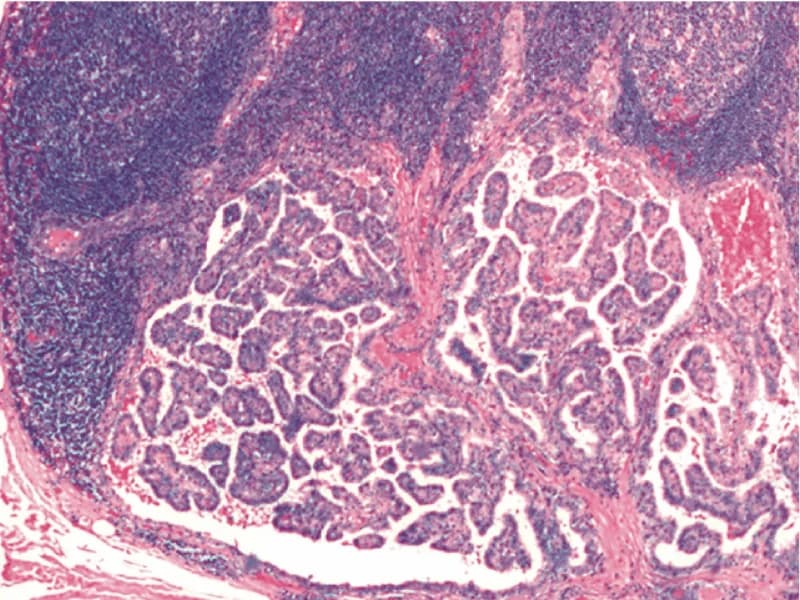

O bócio mergulhante pode afetar a qualidade de vida dos pacientes. Acompanhe passo a passo a cirurgia para a remoção desse tipo de bócio ▶Dr. Jônatas Catunda Cirurgião de cabeça e pescoço CRM 14951 RQE 8522 ▶Esse canal é meramente educacional. Não deve ser utilizado para realizar autodiagnóstico ou auto tratamento! ▶Respeito todas as resoluções do Conselho Federal de Medicina - os vídeos têm somente caráter de prestar informações de fins estritamente educativo e não são divulgados endereço ou telefone de consultório, clínica ou serviço. Seja membro do canal e veja vídeos exclusivos: https://www.youtube.com/channel/UCpL7uBcRElpdP7yEb-9vcgA/join Inscreva-se no canal! http://bit.ly/2FfNPIn Site - https://drjonatascatunda.com Instagram - @drjonatascatunda Consulta online - https://drjonatascatunda.com/consultaonline Whatsapp - 85 98107.2268 #tireoide Nesse canal você vai encontrar muita informação de qualidade sobre as doenças da tireoide como hipotireoidismo, hipertiroidismo, câncer de tireoide, nódulos na tireoide. E também sobre temas variados da especialidade cirurgia de cabeça e pescoço com câncer de boca, de laringe, linfonodos aumentados no pescoço! Produzidos por um especialista no assunto, Dr Jônatas Catunda, cirurgião de cabeça e pescoço, professor universitário de Anatomia humana, mestre em cirurgia pela UFC, doutorando pela UFC.